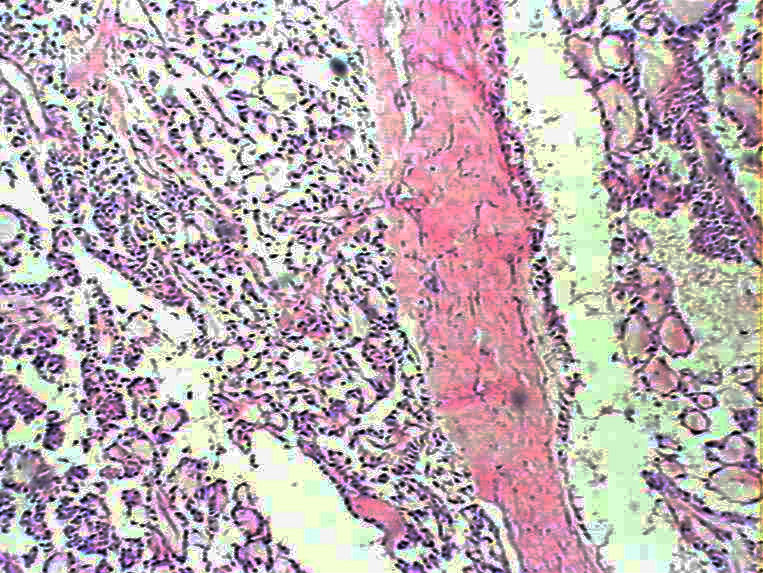

女48 骶尾部皮下见一结节状肿物,,9*6*4cm,切面实性,分叶状,灰白灰红灰黄色,质软。

• 骶尾部肿瘤图1

图1

• 骶尾部肿瘤图2

图2

粘液性室管膜瘤

粘液乳头状室管膜瘤,

是粘液乳头状室管膜瘤,但是楼主提供相关病史、临床资料不能少

会诊粘液乳头状室管膜瘤

骶尾部可以有原发的室管膜瘤,并不一定是转移的

HE切片质量有待提高,但是这个部位,这种乳头状机构,诊断粘液样乳头状室管膜瘤没有问题。